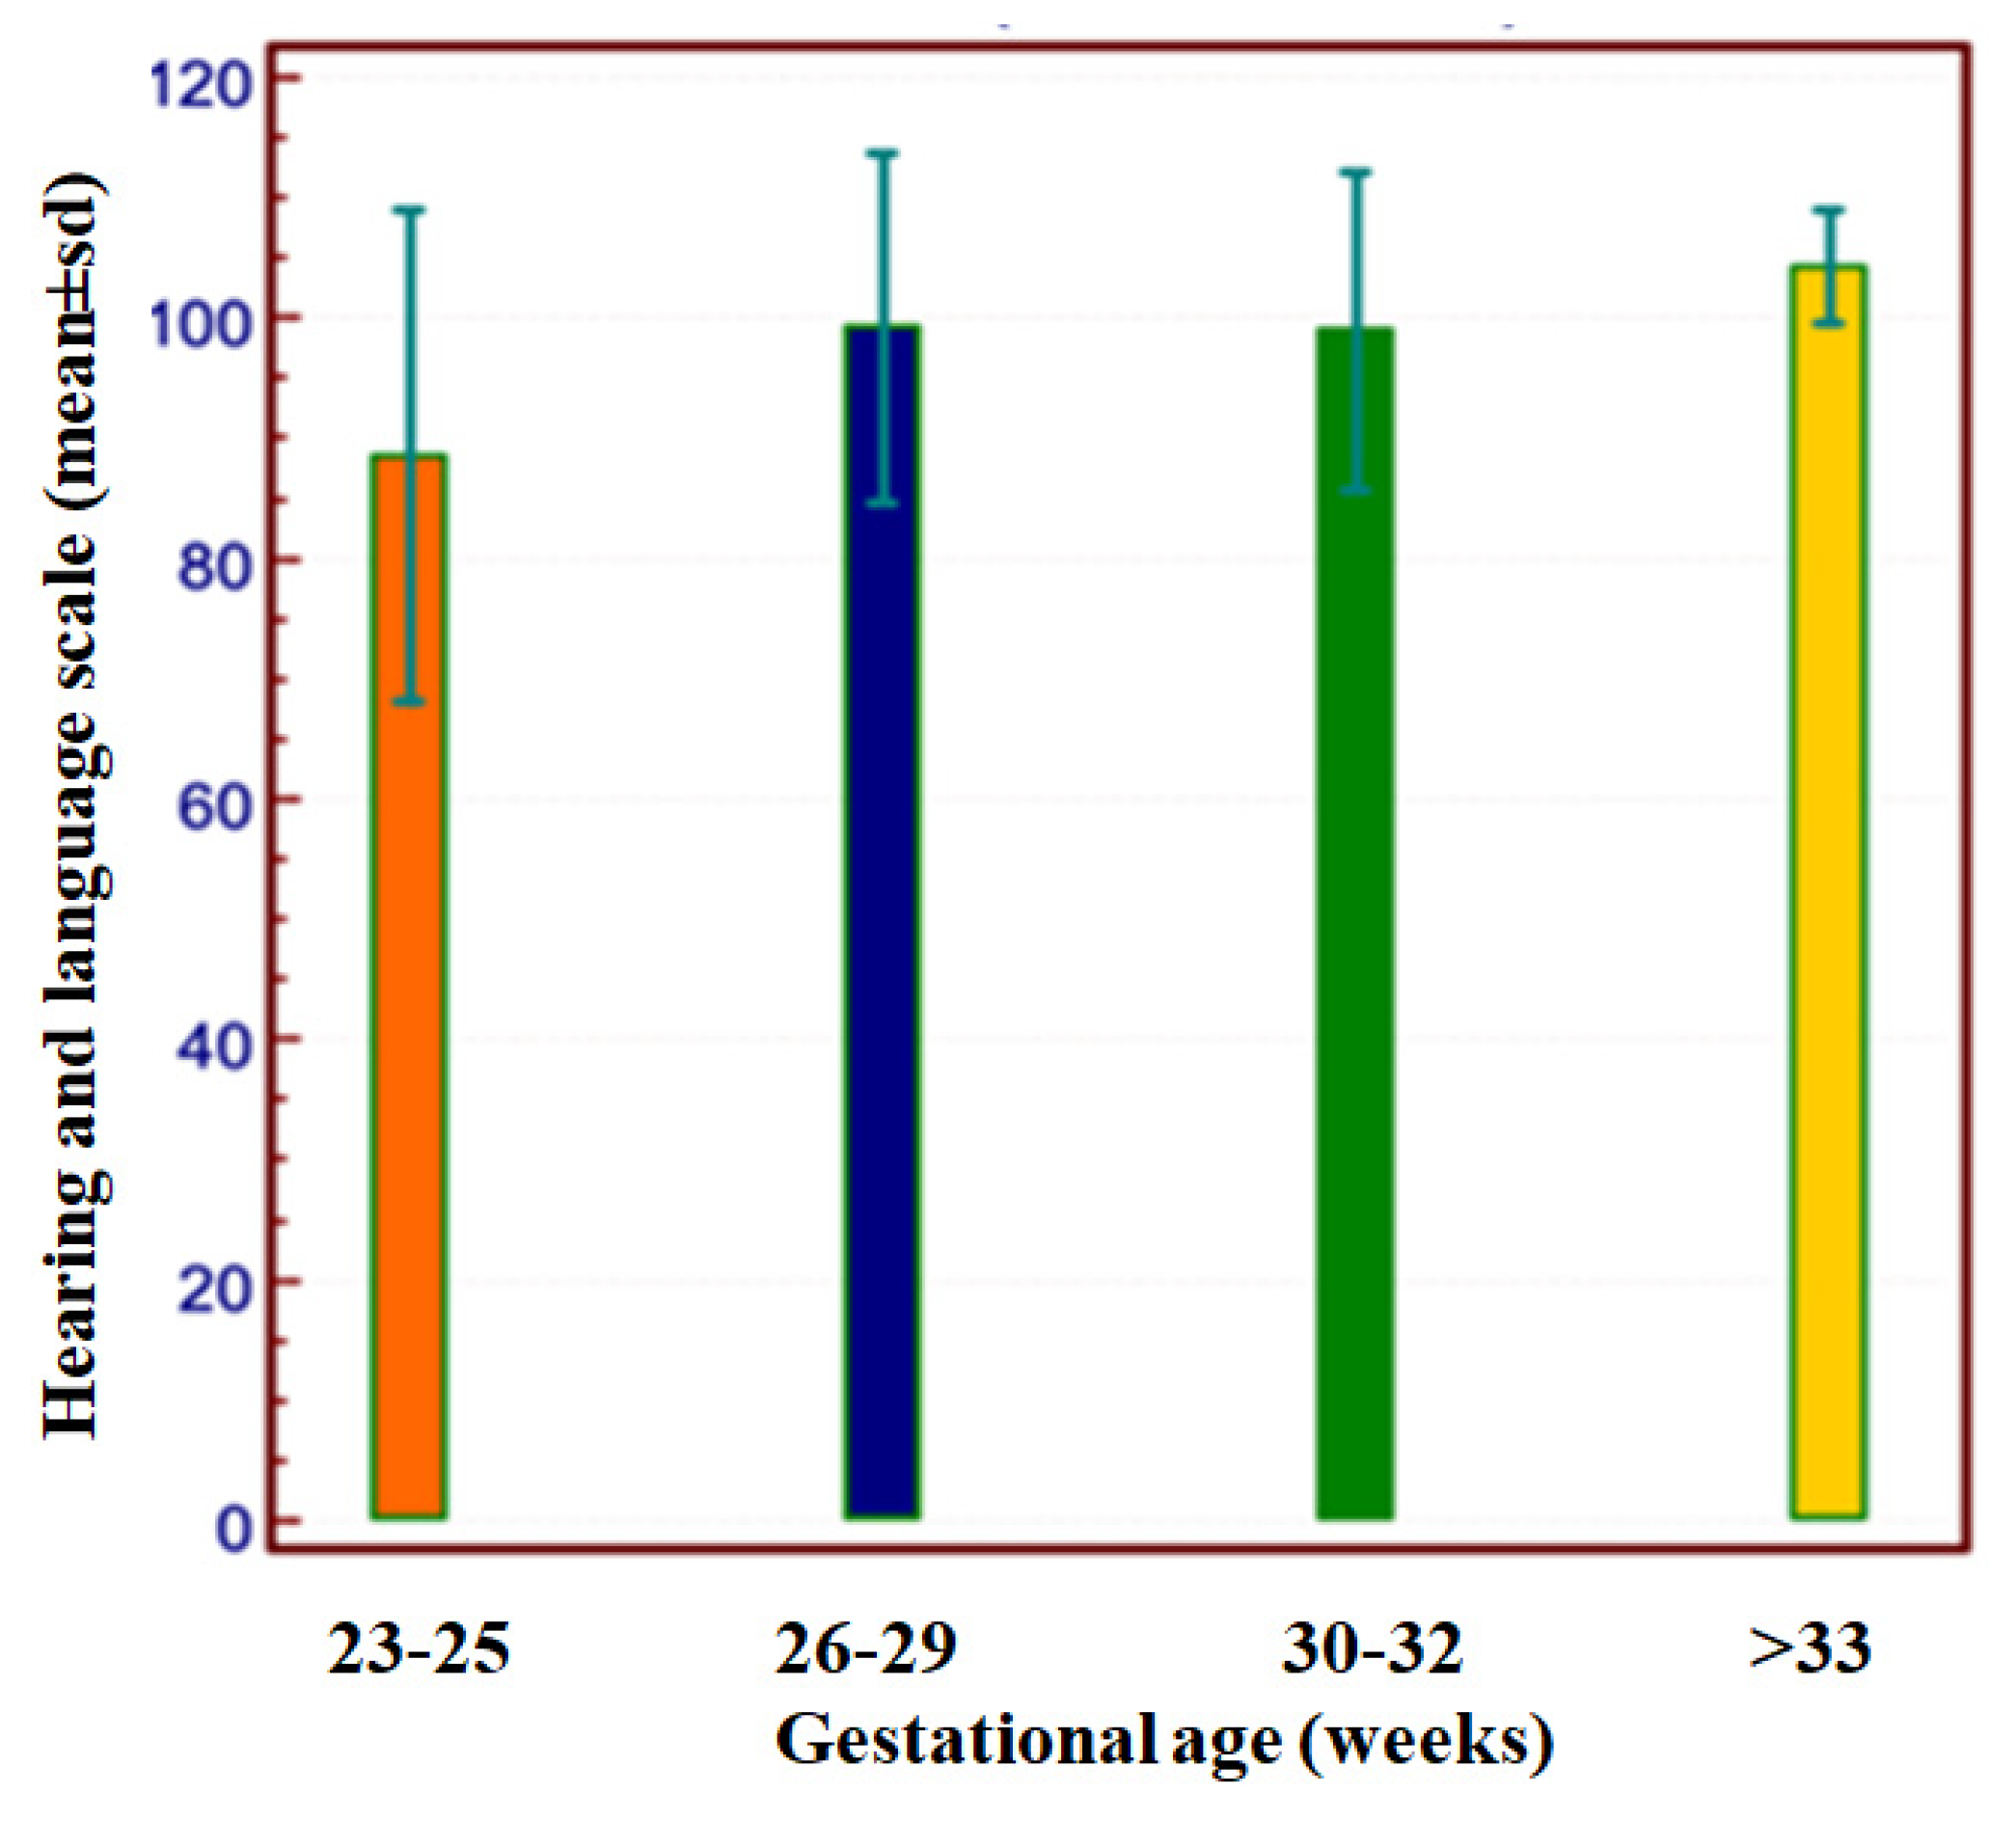

- Barnes-Davis, M.E.; Williamson, B.J.; Merhar, S.L.; Holland, S.K.; Kadis, D.S. Extremely preterm children exhibit altered cortical thickness in language areas. Sci. Rep. 2020, 10, 10824. [Google Scholar] [CrossRef]

- Barre, N.; Morgan, A.; Doyle, L.W.; Anderson, P.J. Language abilities in children who were very preterm and/or very low birth weight: A meta-analysis. J. Pediatr. 2011, 158, 766–774.e1. [Google Scholar] [CrossRef]

- Nguyen, T.N.; Spencer-Smith, M.; Haebich, K.M.; Burnett, A.; Scratch, S.E.; Cheong, J.L.Y.; Doyle, L.W.; Wiley, J.F.; Anderson, P.J. Language Trajectories of Children Born Very Preterm and Full Term from Early to Late Childhood. J. Pediatr. 2018, 202, 86–91.e1. [Google Scholar] [CrossRef]

- Van Noort-van der Spek, I.L.; Franken, M.C.; Weisglas-Kuperus, N. Language functions in preterm-born children: A systematic review and meta-analysis. Pediatrics 2012, 129, 745–754. [Google Scholar] [CrossRef]